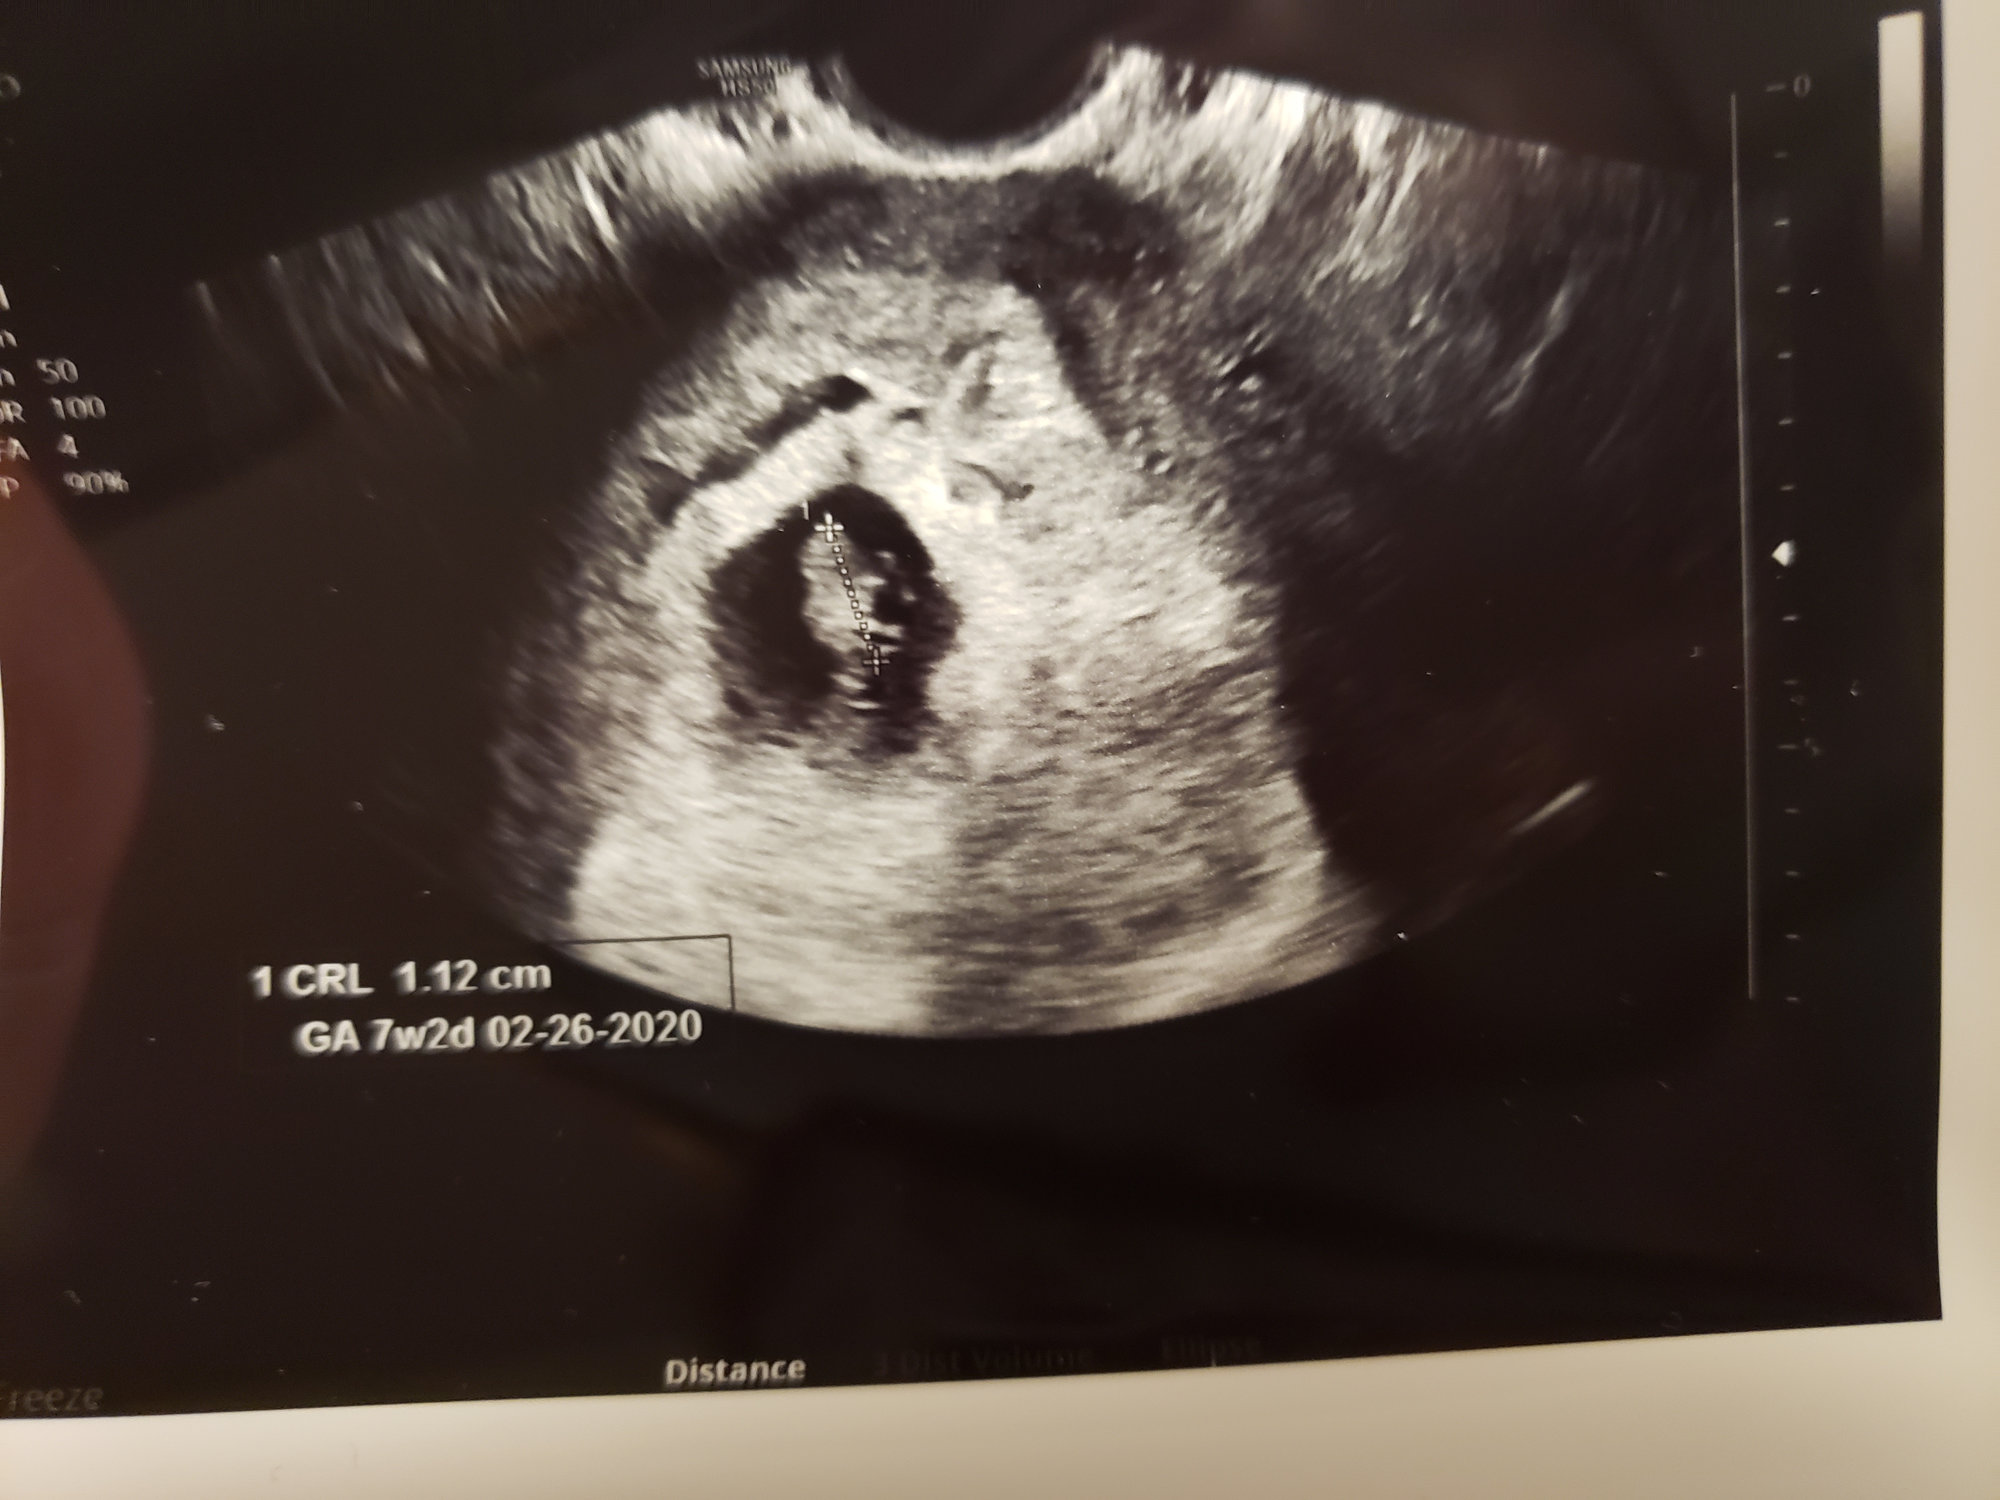

Measuring about a week behind what I expected (7 weeks 1 day not 8 weeks 1 day!) New due days is 2/27/2020!

Baby's heartrate was 150 and doc said everything looked good!

I do have slightly high blood pressure, but we aren't sure if it's white coat syndrome or an ongoing issue but she gave me a prescription for a blood pressure cuff and said to check it daily and send her a log before the next appointment.

I sent this photo to my husband and his response was "I'm not getting teary eyed, you're getting teary eyed!!" ❤